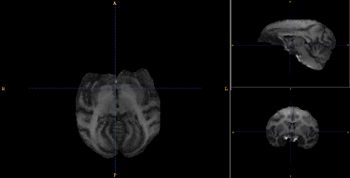

| − | Image:GMtemplate_Cr.jpg|Probabilistic map of GM for Rhesus population | + | Image:GMtemplate_Cr.jpg|Probabilistic map of GM for Rhesus population|left |

- Using a rhesus tissue atlas provided by the UNC Neuro Image Analysis Laboratory and the UWisc Harlow Primate Laboratory we have segmented the data into WM/GM, and CSF capartments using the Lobulated EM Segmentation method. These segmentations have been averaged to create a study-specific tissue atlas.

- Rhesus Probabilistic Atlas